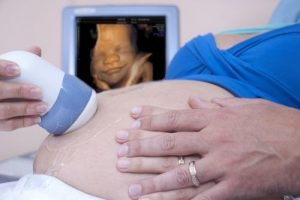

Una donna si sente madre quando, alla prima ecografia, non riesce a trattenere le lacrime di gioia sentendo il cuore di suo figlio battere all’impazzata proprio come il suo, che trabocca di felicità per questo primo contatto.

Tuttavia, per almeno nove mesi bisogna accontentarsi delle ecografie e dei piccoli movimenti del feto, che diventerà sempre più attivo.

Forse, da questo nasce la necessità di una madre di connettersi con la vita che batte dentro di lei. Per questo motivo, nei momenti di riposo, mantiene il contatto accarezzandosi la pancia, parlando con il piccolo in maniera dolce e, a volte, cantando una ninna nanna.